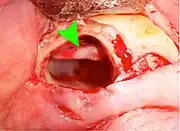

Coronectomy

Coronectomy is a procedure where the crown of the impacted wisdom tooth is removed, but the roots are intentionally left in place. It is indicated when there is no disease of the dental pulp or infection around the crown of the tooth, and there is a high risk of inferior alveolar nerve injury.[31]

Coronectomy, while lessening the immediate risk to the inferior alveolar nerve function has its own complication rates and can result in repeated surgeries. Between 2.3% and 38.3% of roots loosen during the procedure and need to be removed and up to 4.9% of cases require reoperation due to persistent pain, root exposure or persistent infection. The roots have also been reported to migrate in 13.2% to 85.9% of cases.[31]